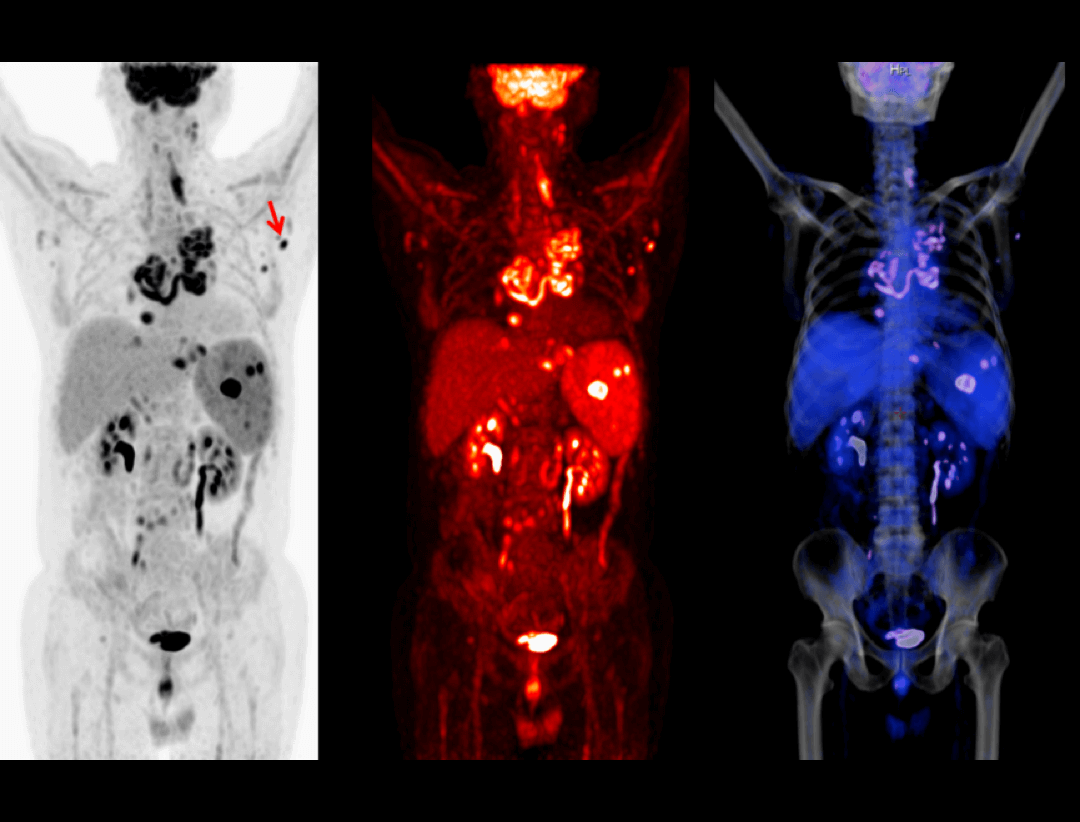

Integrated Oncology Application

The uMI 550 offers a comprehensive solution package for tumor diagnosis and post-therapeutic evaluation on the operation console.